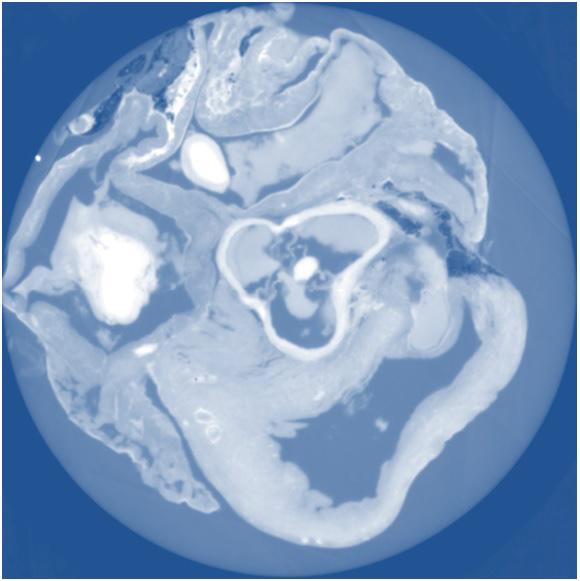

WASHINGTON, D.C., October 21, 2014 -- X-ray phase tomography is an imaging technique that uses penetrating X-rays to create volumetric views through "slices" or sections of soft biological tissues, such as tumors, and it offers strongly enhanced contrast compared to conventional CT scans. Yet scientists still do not know which X-ray phase tomography methods are best suited to yield optimized results for a wide variety of conditions.

To answer this question, a large group of researchers in Europe set out to compare three different X-ray phase tomography methods at the European Synchrotron Radiation Facility's (ESRF) beamline ID19 in France—X-ray grating interferometry, propagation-based phase tomography with single-distance phase reconstruction, and holotomography.

Led by Irene Zanette, a scientist affiliated with both ESRF and the Technische Universität München (TUM) in Germany, the researchers put these three techniques to the test by examining cancerous tissue from a mouse model and an entire rat's heart, which they report this week in the Journal of Applied Physics , from AIP Publishing.

So what did they find by comparing methods? The group was able to show that for each specimen, the spatial resolution derived from the characteristic morphological features is about twice as good for holotomography and single-distance phase reconstruction compared to X-ray grating interferometry. They also found that X-ray grating interferometry data generally provide much better contrast-to-noise ratios for anatomical features, excel in fidelity of the density measurements, and are more robust against low-frequency artifacts than holotomography.